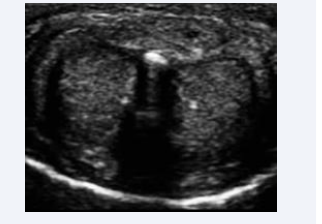

Penile calciphylaxis was diagnosed as a result of chronic kidney disease and diabetes after reduced blood flow consistent with vascular calcification was documented through Doppler ultrasound [Figure 2].

Doppler ultrasound revealed evidence of vascular  calcification. (Arrow).

Figure 2: Doppler ultrasound revealed evidence of vascular calcification. (Arrow).